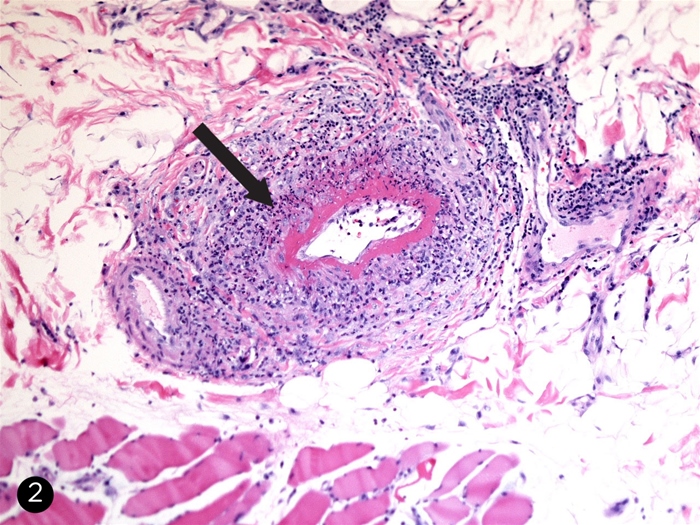

• Pulmonary parenchymal involvement includes nodular opacities, consolidations, and cavitary pulmonary infiltrates representing areas of lung inflammation and necrosis (

image 3

Widespread capillary inflammation can cause diffuse alveolar hemorrhage (DAH), which appears as bilateral alveolar opacification (

image 4